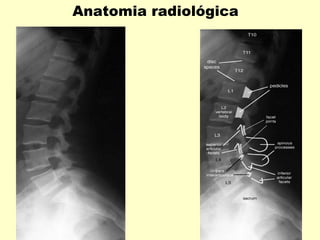

Anatomia radiológica

Incidências Básicas

Radiografias em A P e Perfil .

Para verificações dos forames intervertebrais

como também para avaliação dos arcos

posteriores , acrescentar incidências obliquas.

Para avaliações de eixo vertebral

acrescentar radiografias dinâmicas

em hiperextensão e hiperflexão.